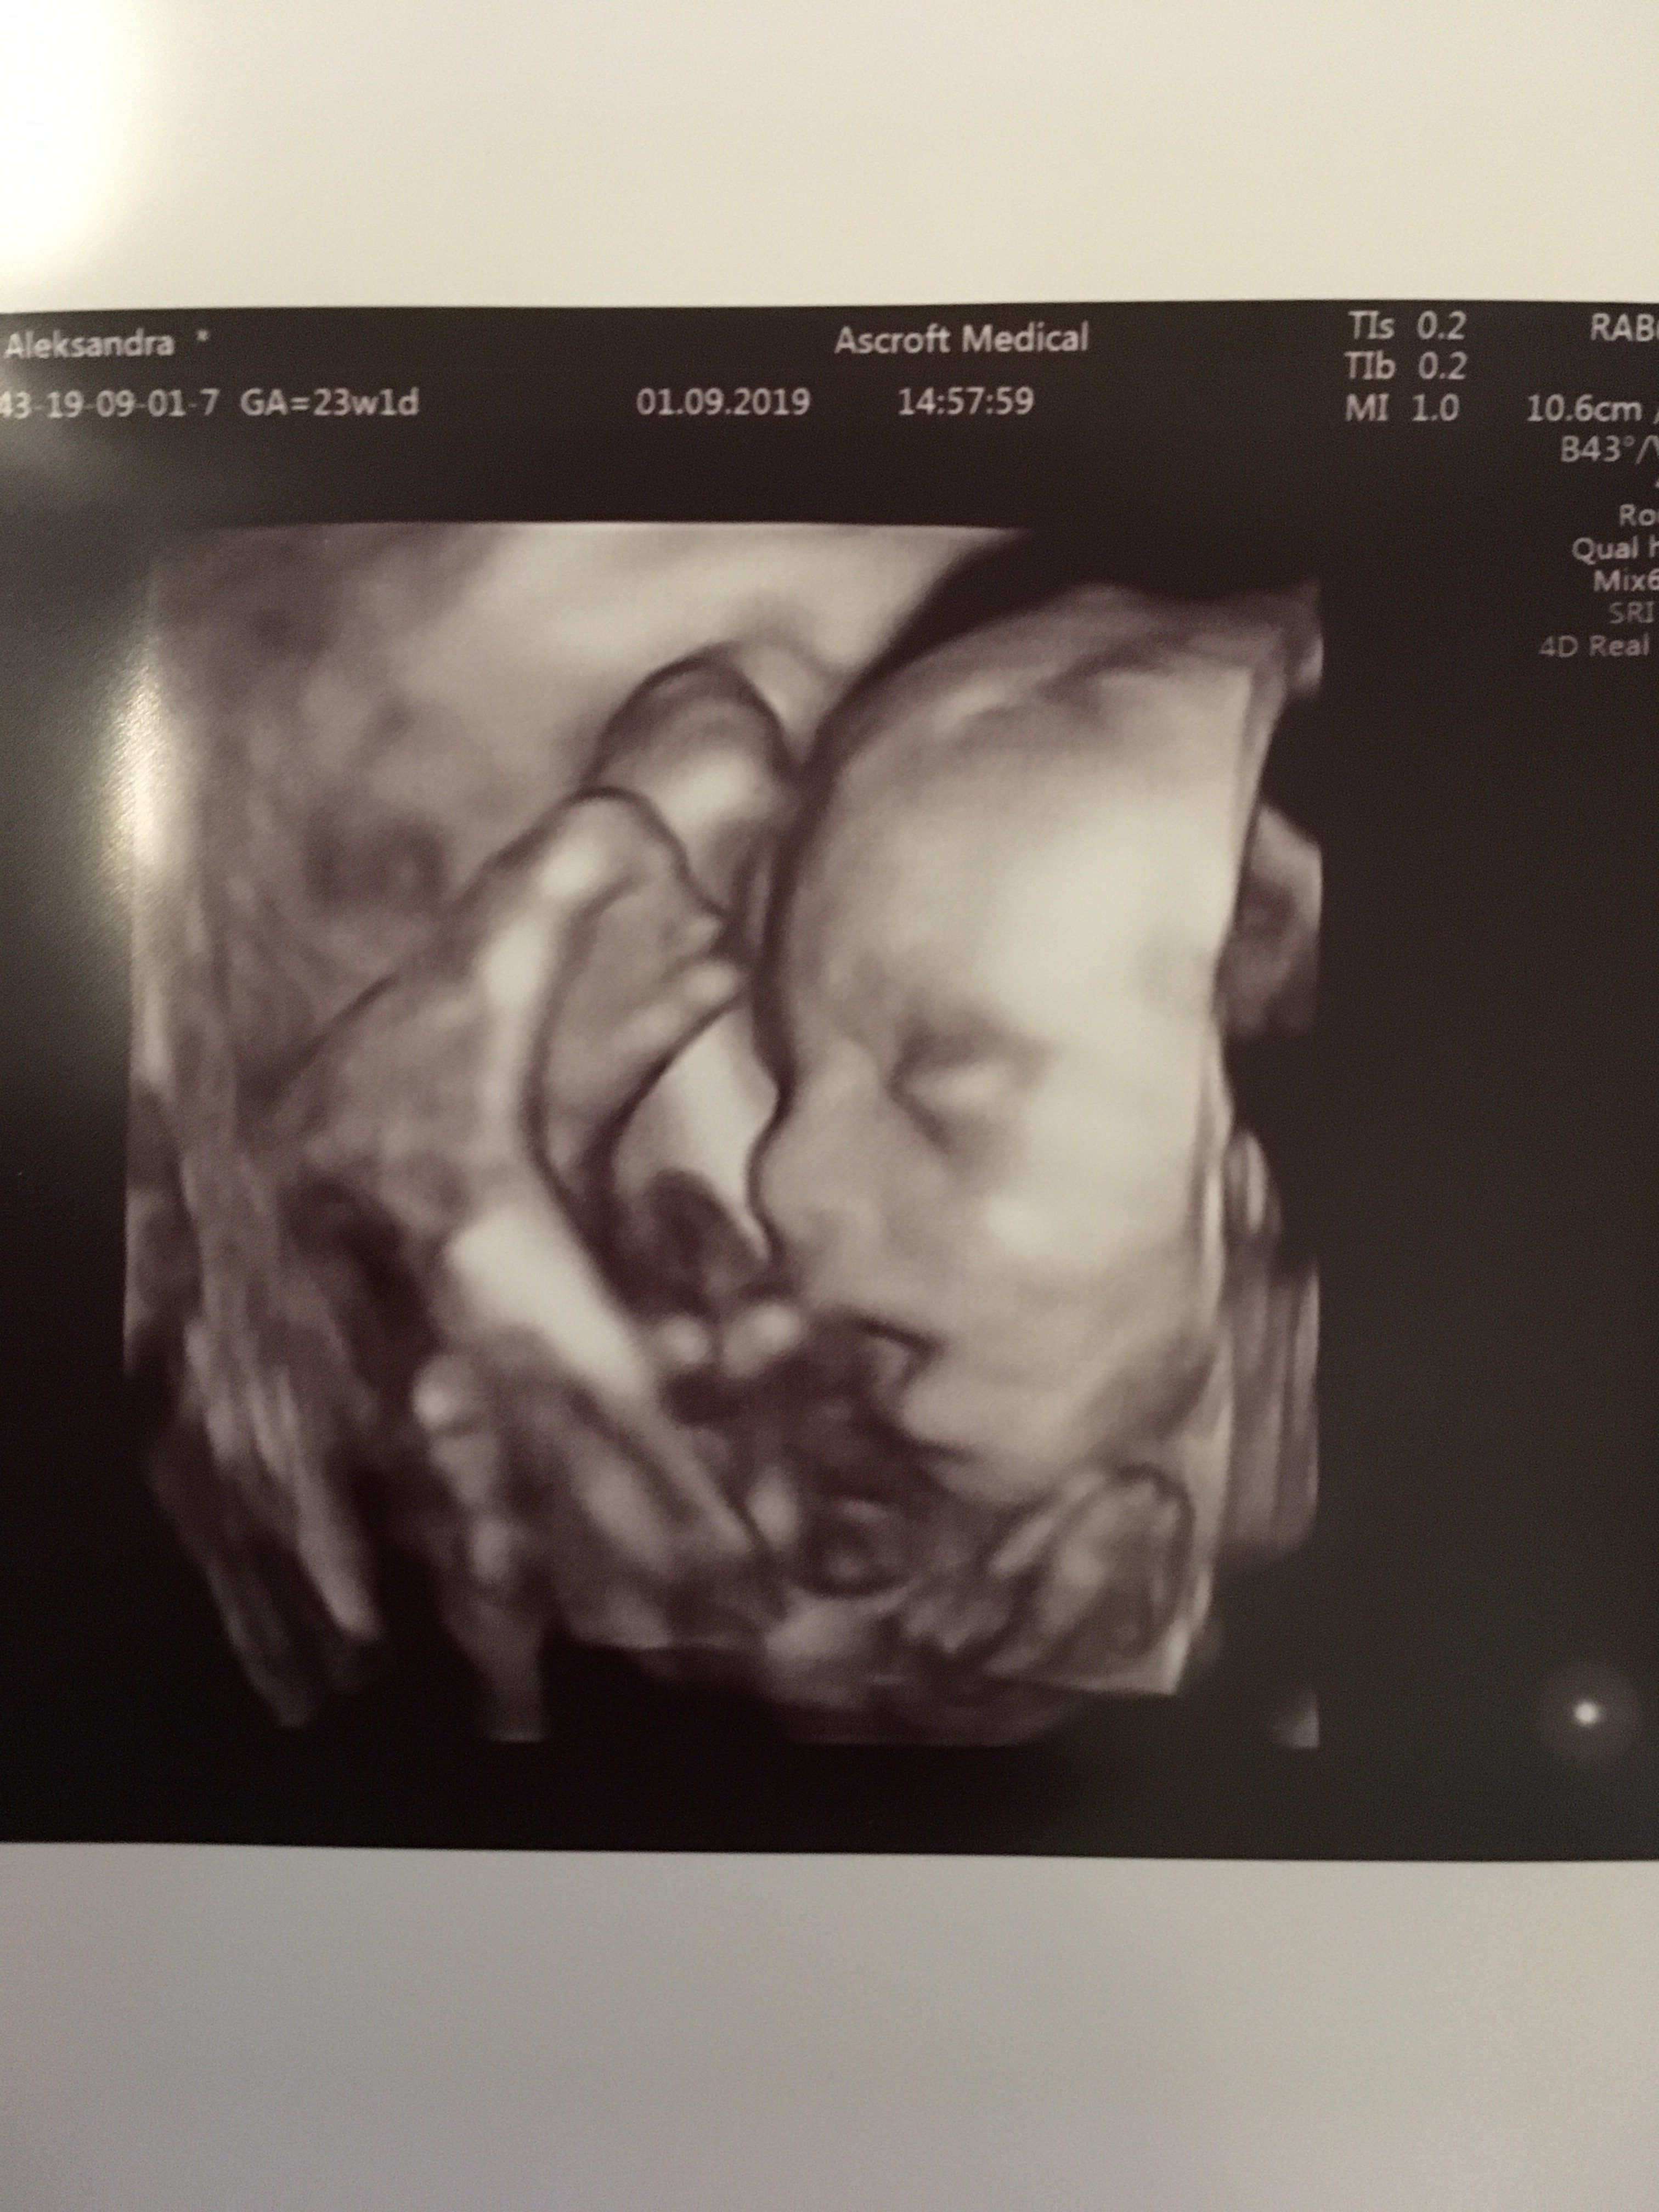

Mój synek tak wyglada w 3D :D cały czas gryzł pępowinę:biggrin2: